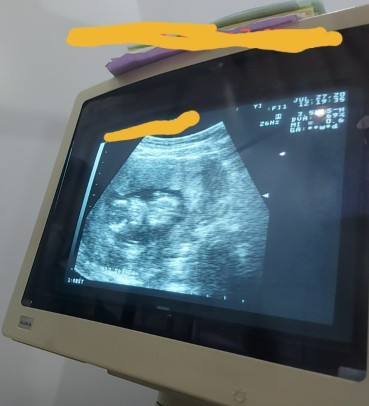

Hi po.1st time mom po. Okay lang po ba ang result ng ultrasound ko? Kunti lang po ba ang water ko? 13weeks and 3 days po eto. Ano pa po ba ang way para dumami ang tubig? Thank you po

Momshie sure ka ba na konti ang amniotic fluid mo po? Dapat po may advise ang OBGYN ninyo if kakaunti nga ang panubigan ninyo based diyan sa UTZ result ninyo. 🙂